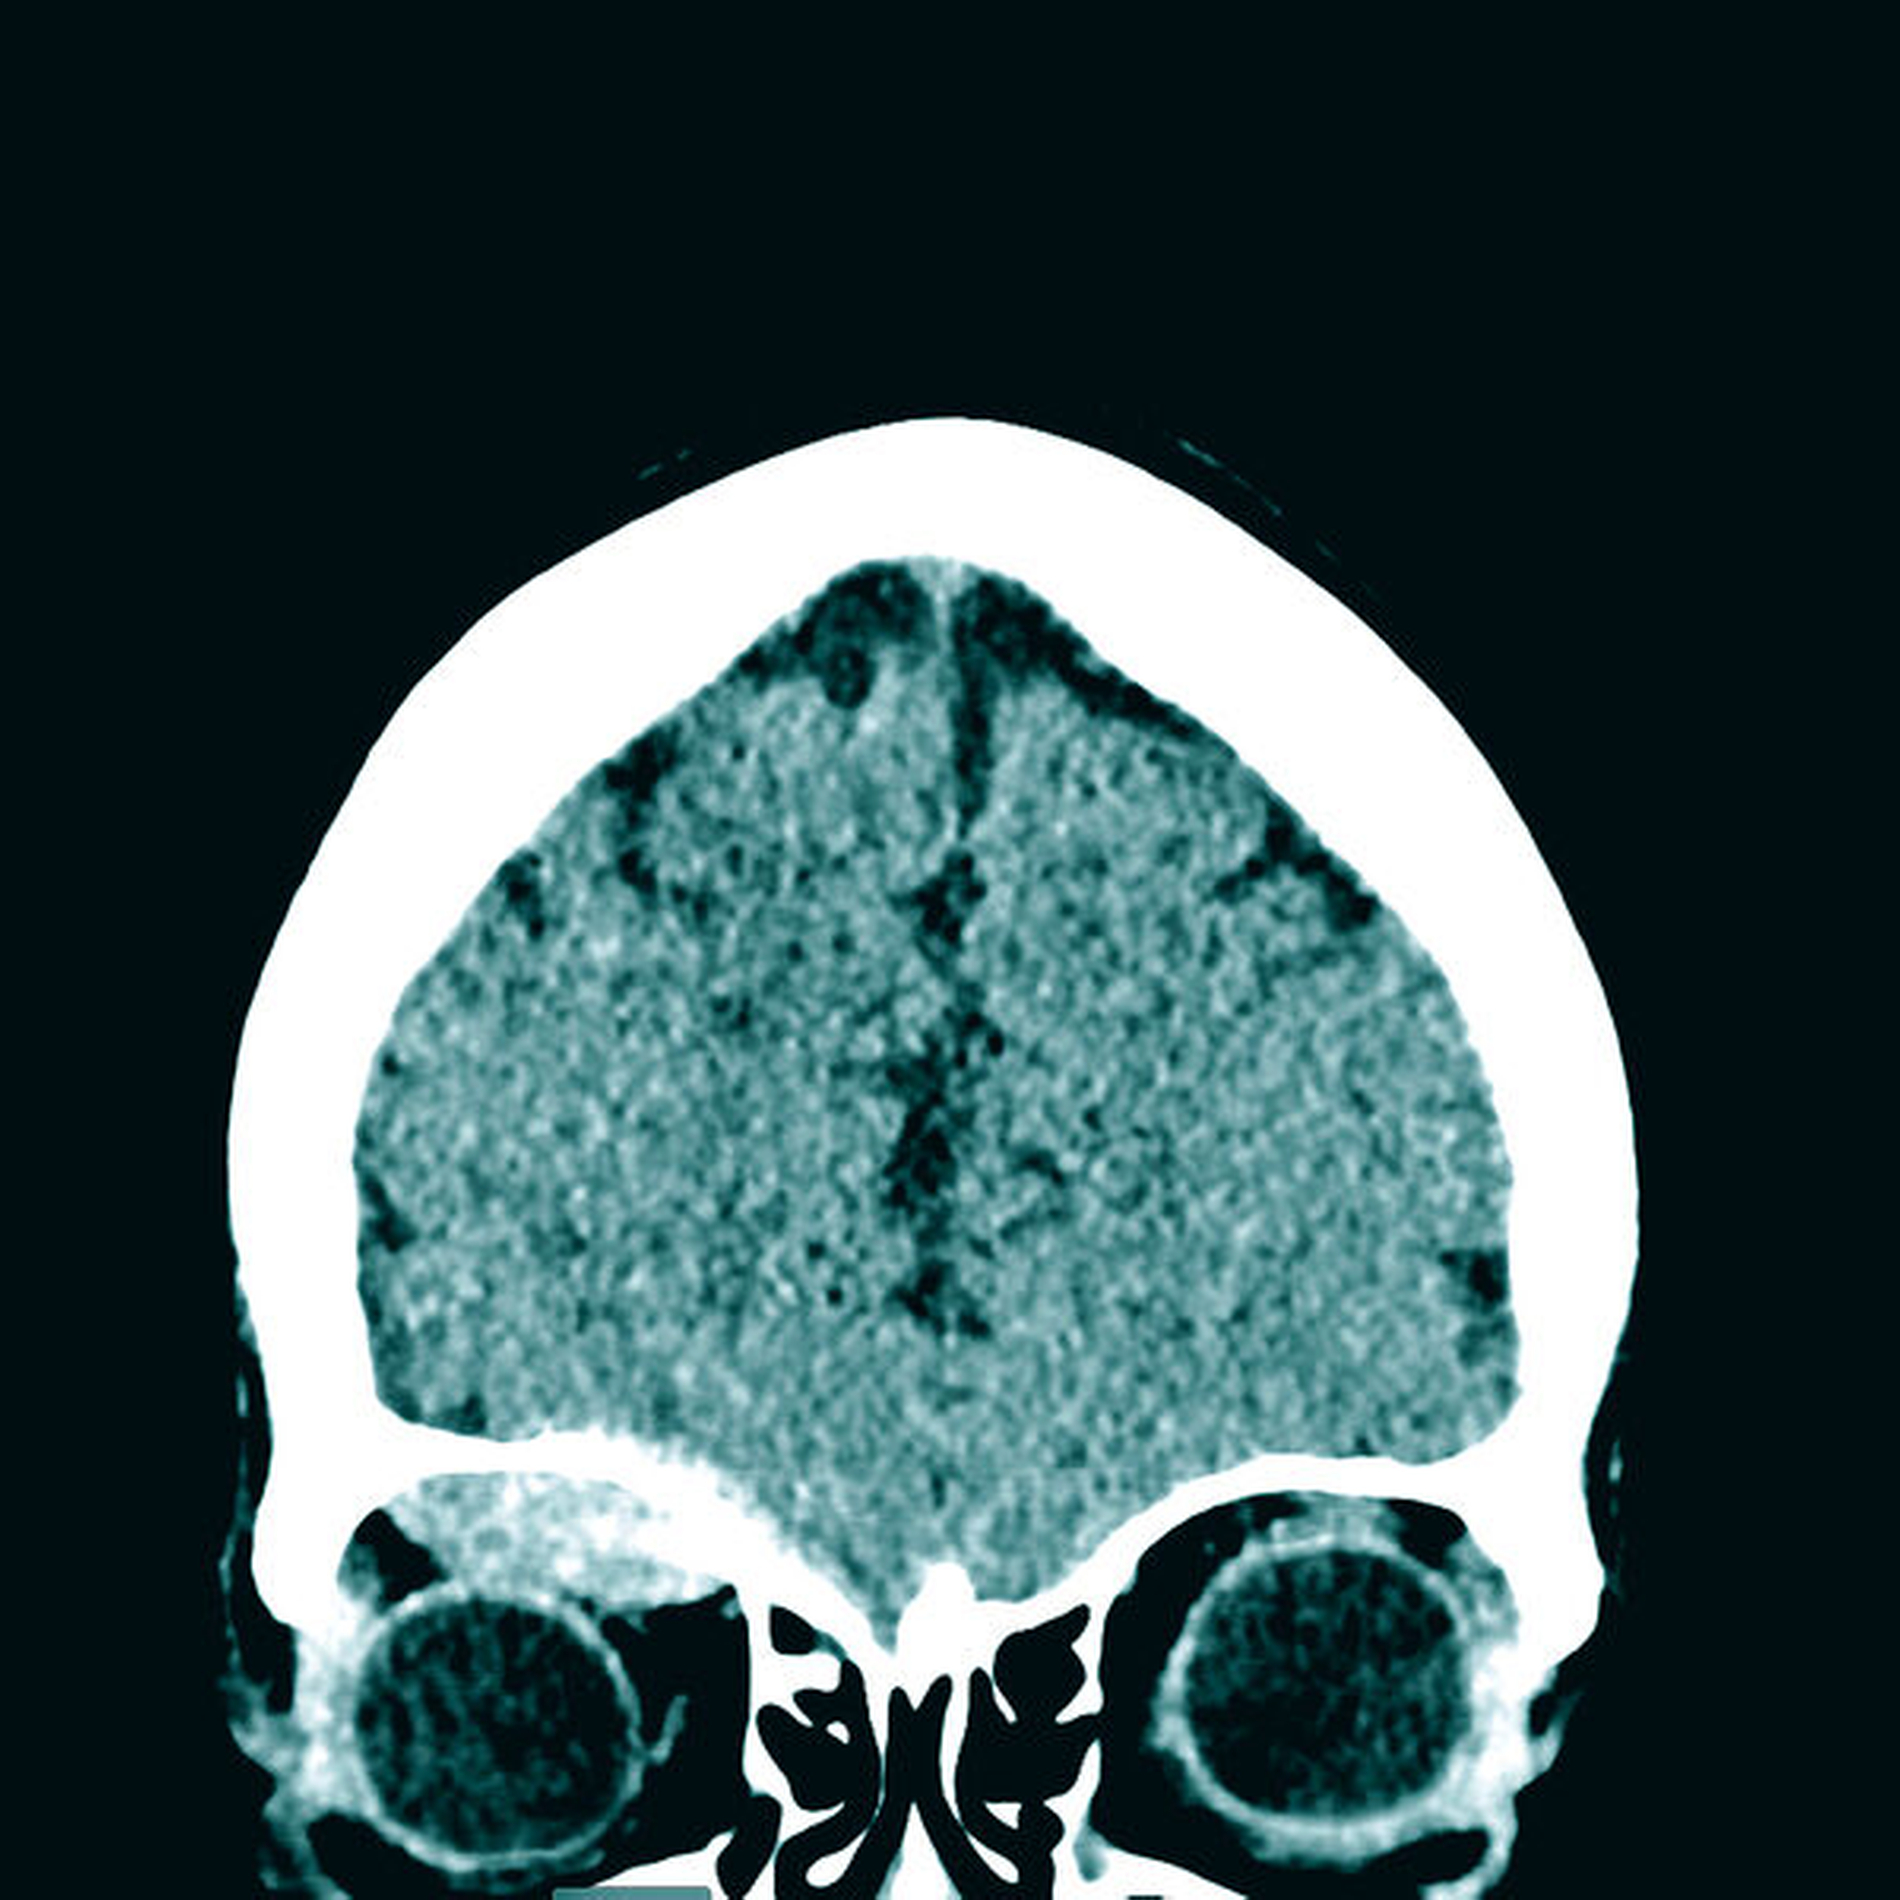

Zur weiteren Diagnostik erfolgte die Anfertigung einer Computertomografie des Schädels. Hier zeigte sich neben einem rechtsseitig temporalen Epiduralhämatom und einer Felsenbeinfraktur ein subperiostal gelegenes Orbitahämatom ohne Zeichen einer Optikuskompression (Abbildung 1). Eine Mitbeurteilung durch die ophthalmologischen Kollegen der Universitätsmedizin ergab keinen akuten Interventionsbedarf.

In der Zusammenschau der Befunde wurde sich in enger Absprache zwischen der Patientin, dem behandelnden Neurochirurgen und dem zuständigen Mund-, Kiefer- und Gesichtschirurgen zunächst für ein konservatives Therapieregime mit engmaschiger Überwachung der Glasgow-Koma-Skala, stündlichen Visuskontrollen und einer erneuten Verlaufscomputertomografie entschieden. Die Re-Computertomografie nach vier Stunden zeigte einen stabilen Befund sowohl des Epiduralhämatoms als auch des Orbitahämatoms, so dass auch nach erneuter Bildgebung und weiterhin fehlender klinischer Symptomatik der Patientin keine Indikation zu einer chirurgischen Intervention notwendig war.